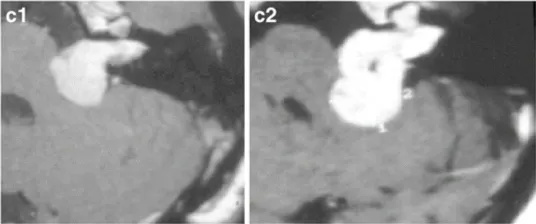

下图显示了放射治疗失败的其他病例,与这些患者相比,这些患者表现出更快的肿瘤再生长和更严重的临床症状(图3a–c)。由于脑干受压增加,这些病例都需要在伽玛刀治疗后3年内进行显微手术切除。图3d–f展示了立体定向放射治疗(SRT)之后的一些放射学变化。

d-44岁女性。增强后轴向MRI显示右侧中等大小的肿瘤,有明显的囊肿形成(伽马刀治疗后2年)。

e-36岁女性。增强后轴向磁共振成像显示左侧较大肿瘤,在不适当的三次伽马刀治疗后明显压迫脑干。

f-42岁男性。FLAIR轴向磁共振成像显示右侧大肿瘤,伽马刀治疗后小脑明显受损